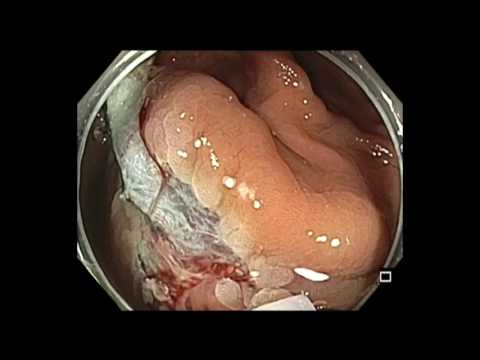

Siedzący gruczolak ząbkowany kątnicy

Film przedstawia zabieg usunięcia polipa typu SSA usytuowanego w kątnicy.